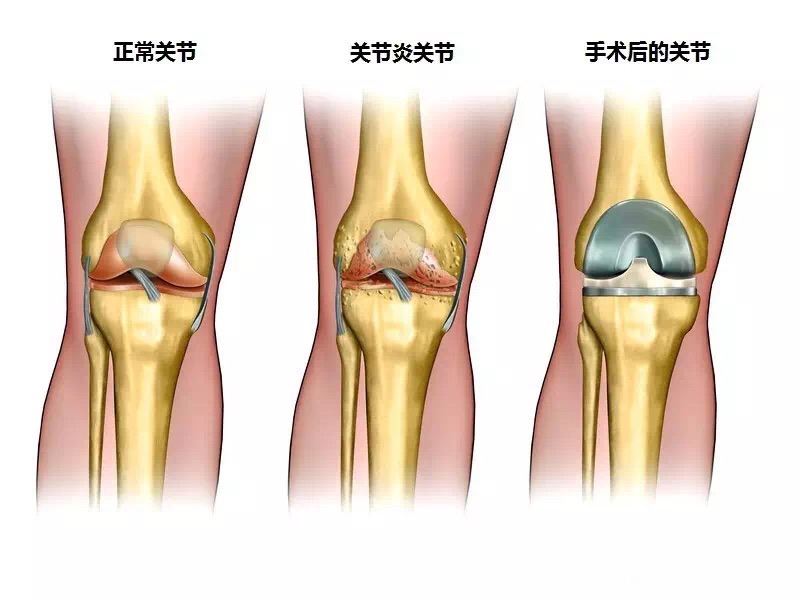

我有一个治疗膝关节炎的效方,用了很多年,临床上疗效显著,特献出来与大家共勉,请广大博友验证。药物组成:大黄,马钱子,威灵仙,伸筋草,透骨草,忍冬藤,桂枝,红花,独活,牛膝,当归,生川乌,生草乌,白花蛇舌草,五加皮,刘寄奴,羌活,骨碎补各15克,白芥子5克,研细末备用,以白酒,醋调成膏药外敷患处,上面覆盖保鲜膜,用TDP照射,每次一小时,每天一次,两周一疗程。

膝关节炎的针灸治疗配穴:双膝眼 鹤顶 阴陵泉 阿是穴 委中 委阳 三阴交等

膝关节炎的针灸治疗行痹:风门、肝俞、膈俞;痛痹:大椎、关元;着痹:脾俞、中脘、阴陵泉;热痹:曲池、合谷。

这是我在临床上常用的针灸处方,请各位在临床上辨证加减,在针灸背俞穴位时候,大家要谨重,不要深刺,甲乙经有云:腹深如井,背薄如饼,背部的穴位不可深刺,请各位验证另外,我在治疗中又加入了高树中教授的关于治疗膝关节炎的针灸穴位尺泽穴,效果很好